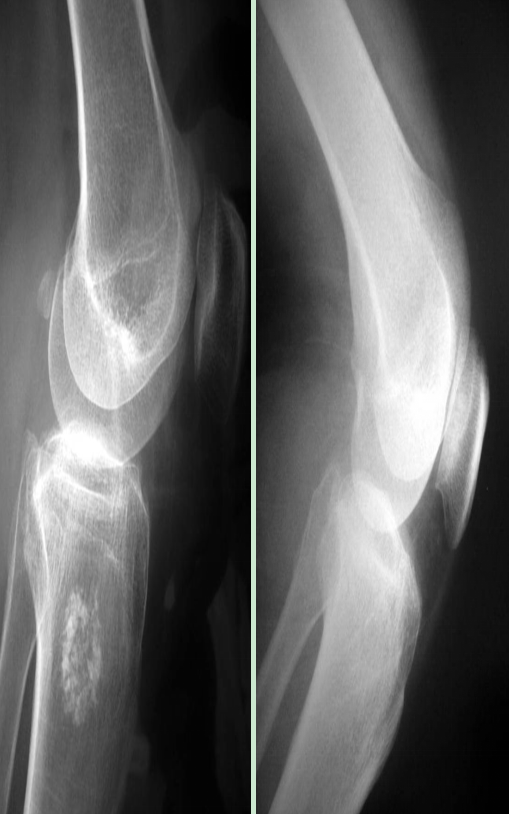

盤影半月板X線片的特征(60%)

高位腓骨頭(與脛骨平臺距離小于10mm,高于骨詬線可疑)。

外側(cè)脛股間隙大(寬、高),股骨外髁有一凹陷的壓跡(大于1mm)、扁平。

外側(cè)脛股間隙外緣骨質(zhì)增生(一般外側(cè)穩(wěn)定,不增生)。

可見左側(cè)高位腓骨小頭、外側(cè)脛骨增生、外側(cè)關(guān)節(jié)間隙較寬高

左側(cè)股骨外髁壓跡大于1mm